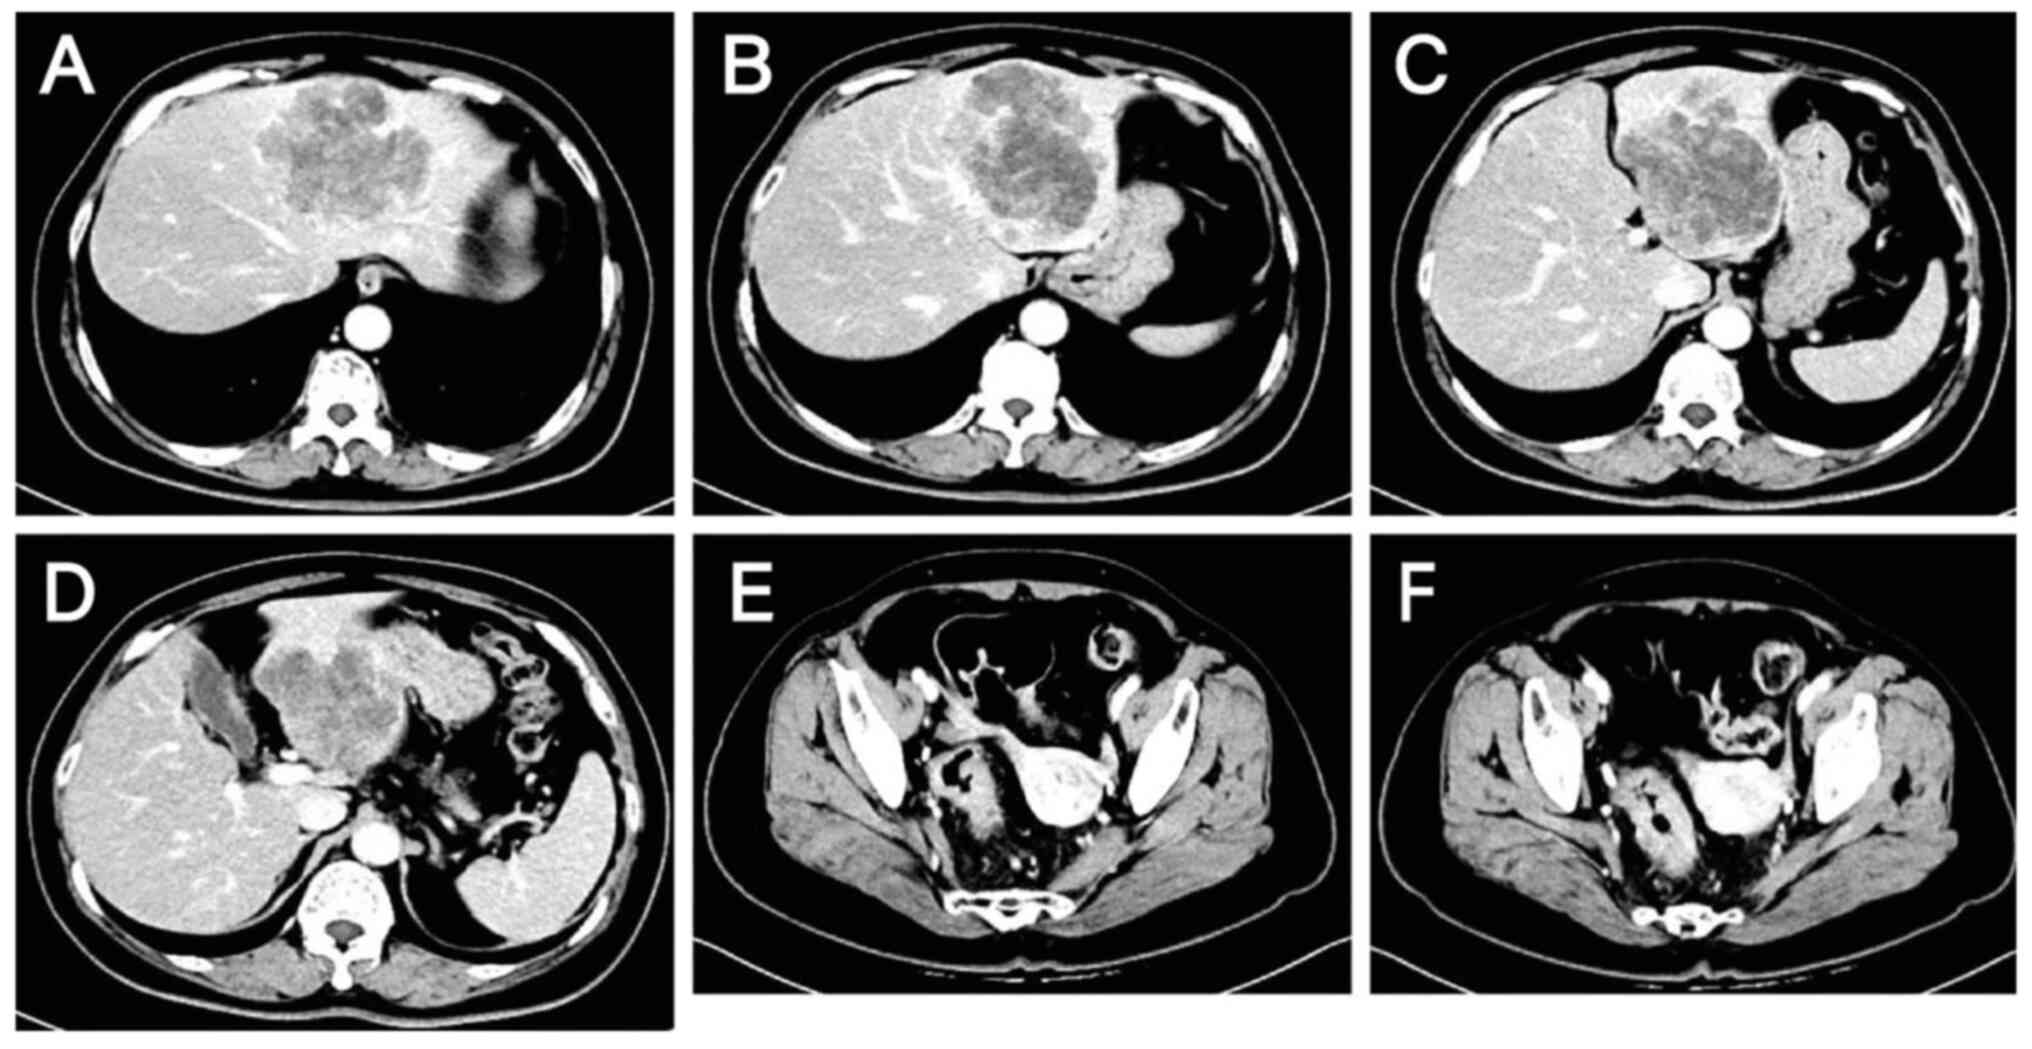

A 60-year-old woman with complaints of abdominal pain and passage of bloody stools was admitted to Hebei General Hospital (Shijiazhuang, China) in October 2023. Contrast-enhanced scans of the abdomen and pelvis revealed wall thickening in the sigmoid colon and rectum, enlarged lymph nodes in the surrounding area suggestive of malignancy, and low-density shadows in the S2, S3 and S4 segments of the liver that were thought to be metastases (Fig. 1). Colonoscopy suggested rectal cancer, and a tissue biopsy revealed moderately and well-differentiated adenocarcinoma with necrosis (Fig. 2). Magnetic resonance images revealed liver metastases in the S2, S3 and S4 segments and two enlarged lymph nodes, one anterior and one posterior to the portal vein (Fig. 3). Digestive tract tumor marker levels, including carcinoembryonic antigen, carbohydrate antigen (CA)242 and CA724, were all higher than normal (Fig. 4). NGS of a biopsy specimen obtained by colonoscopy suggested that KRAS, NRAS and BRAF were WT (Figs. S1 and S2). It also revealed that ERBB2 (HER2) had a mutation abundance 8.3-fold higher than the reference level, suggesting possible resistance to panitumumab and cetuximab. In addition, TP53 exon5c.399del had a mutation abundance of 31.61%, suggesting microsatellite stability. The NGS was performed by Novogene Bioinformatics Technology Co., Ltd. DNA extraction and library preparation was performed using the Qiagen QIAamp DNA FFPE Kit (Qiagen, GmbH) and Agilent SureSelect XT HS2 (Agilent Technologies, Inc.), respectively. Sample quality was assessed by pathological analysis of tumor cell content, nucleic acid quality assessment (total DNA amount, DNA degradation degree and total pre-library amount) and sequencing quality assessment (average sequencing depth, coverage uniformity, genome alignment rate and base quality Q30 proportion). The hybridization capture method was used, and the read length and sequencing direction were double ends of 150 bp and double-end sequencing, respectively. The sequencing platform and sequencing kit were the Illumina NextSeq 550 and Illumina NextSeq 550 High Output kits (Illumina, Inc.), respectively. Final library loading concentration was 1.2–1.8 pM. The software used for the analysis included CNVkit (version 0.9.9; University of California), GATK Mutect2 (version 4.1.8.1; Broad Institute of MIT and Havard) and PierianDx (version 7.3; Velsera, Inc.).

Initial assessment of the lesions by

computed tomography on October 15, 2023. (A-D) Metastatic liver

lesions: Slightly hypodense shadows are visible in the S2, S3 and

S4 segments of the liver, suggestive of metastasis. (E and F) Colon

lesions: Thickening of the sigmoid-rectal wall and enlargement of

the peripheral lymph nodes are indicative of malignancy. Lesions

are indicated by arrows.

Figure 1.

Initial assessment of the lesions by computed tomography on October 15, 2023. (A-D) Metastatic liver lesions: Slightly hypodense shadows are visible in the S2, S3 and S4 segments of the liver, suggestive of metastasis. (E and F) Colon lesions: Thickening of the sigmoid-rectal wall and enlargement of the peripheral lymph nodes are indicative of malignancy. Lesions are indicated by arrows.